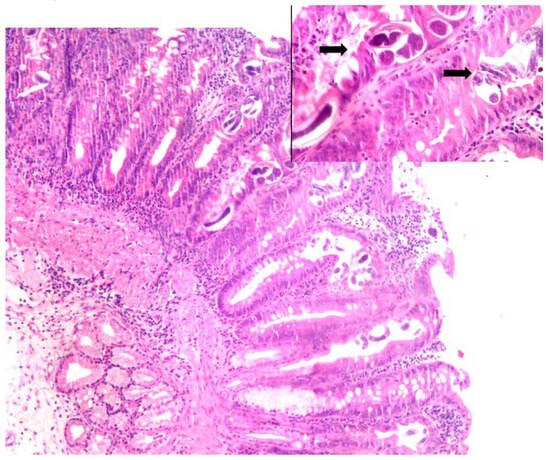

Stool microscopy done by direct wet mount technique showed filariform larvae of S. stercoralis. Histological examination of biopsies of ulcer and lymph node identified parasites with the characteristics of S. stercoralis (Figure 2).

Figure 2.

Duodenal biopsy showing inflammatory exudates with magnified view showing eggs and larvae of Strongyloides in the mucosa and mucosal glands (solid arrows). Hematoxylin and Eosin staining, magnification 40×; inset 100× oil immersion.